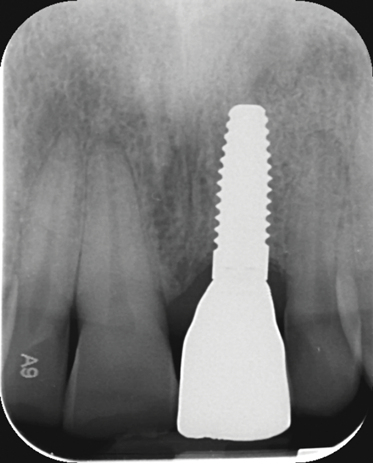

Fig 1. Titanium (left) and zirconia (right) implants.

Figure 1

Fig 8. Insertion of metal-free ceramic implant (4.2 mm x 12 mm) 8 weeks after extraction of hopeless tooth No. 9.

Figure 8